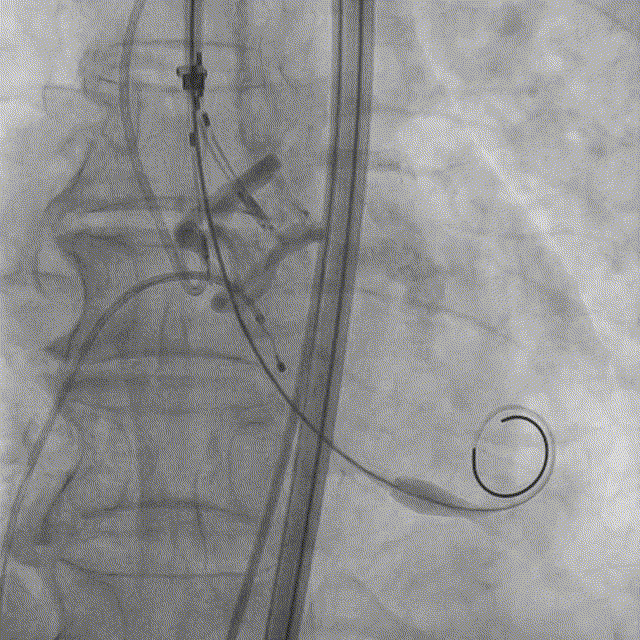

7. 23mm Silara-Valve瓣膜过弓和跨瓣;

8. 23mm Silara - Valve瓣膜左心室初步释放,瓣膜功能良好(不需要左心室快速起搏);

9. Silara - Valve提拉至瓣环水平,精准定位瓣膜,造影剂显示瓣膜功能良好,完成固化;

10. 最终造影瓣膜位置理想,无返流。